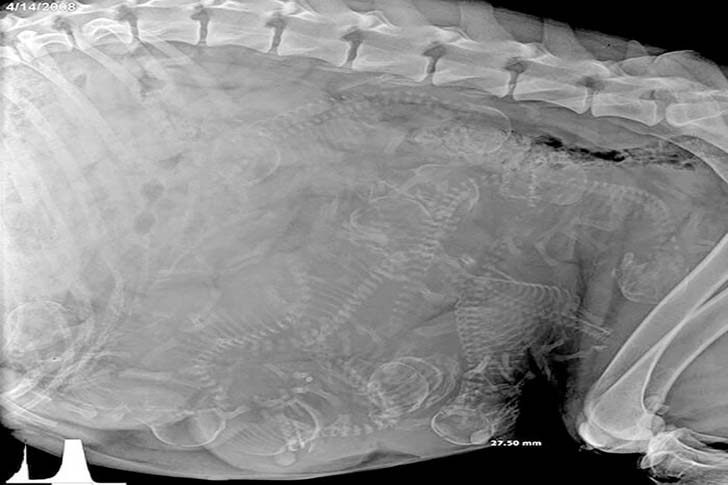

この写真にタイトルが付いていないとして、一つの大きな体の中に無数の小さな骨があるという奇妙な状態を説明するために、あなたの頭の中では様々な可能性が広がっているかもしれません。しかし、その背景を理解すると、実はとても驚くべきことなのです。狭い場所にたくさんの骨が密集していて、これが “自然” であることは衝撃的です。なんとこれからたくさんの子犬が産まれてくるのです!

人間の妊娠中の超音波検査は見慣れた光景ですが、妊娠中のワンちゃんののレントゲン写真には驚かされるばかりです。